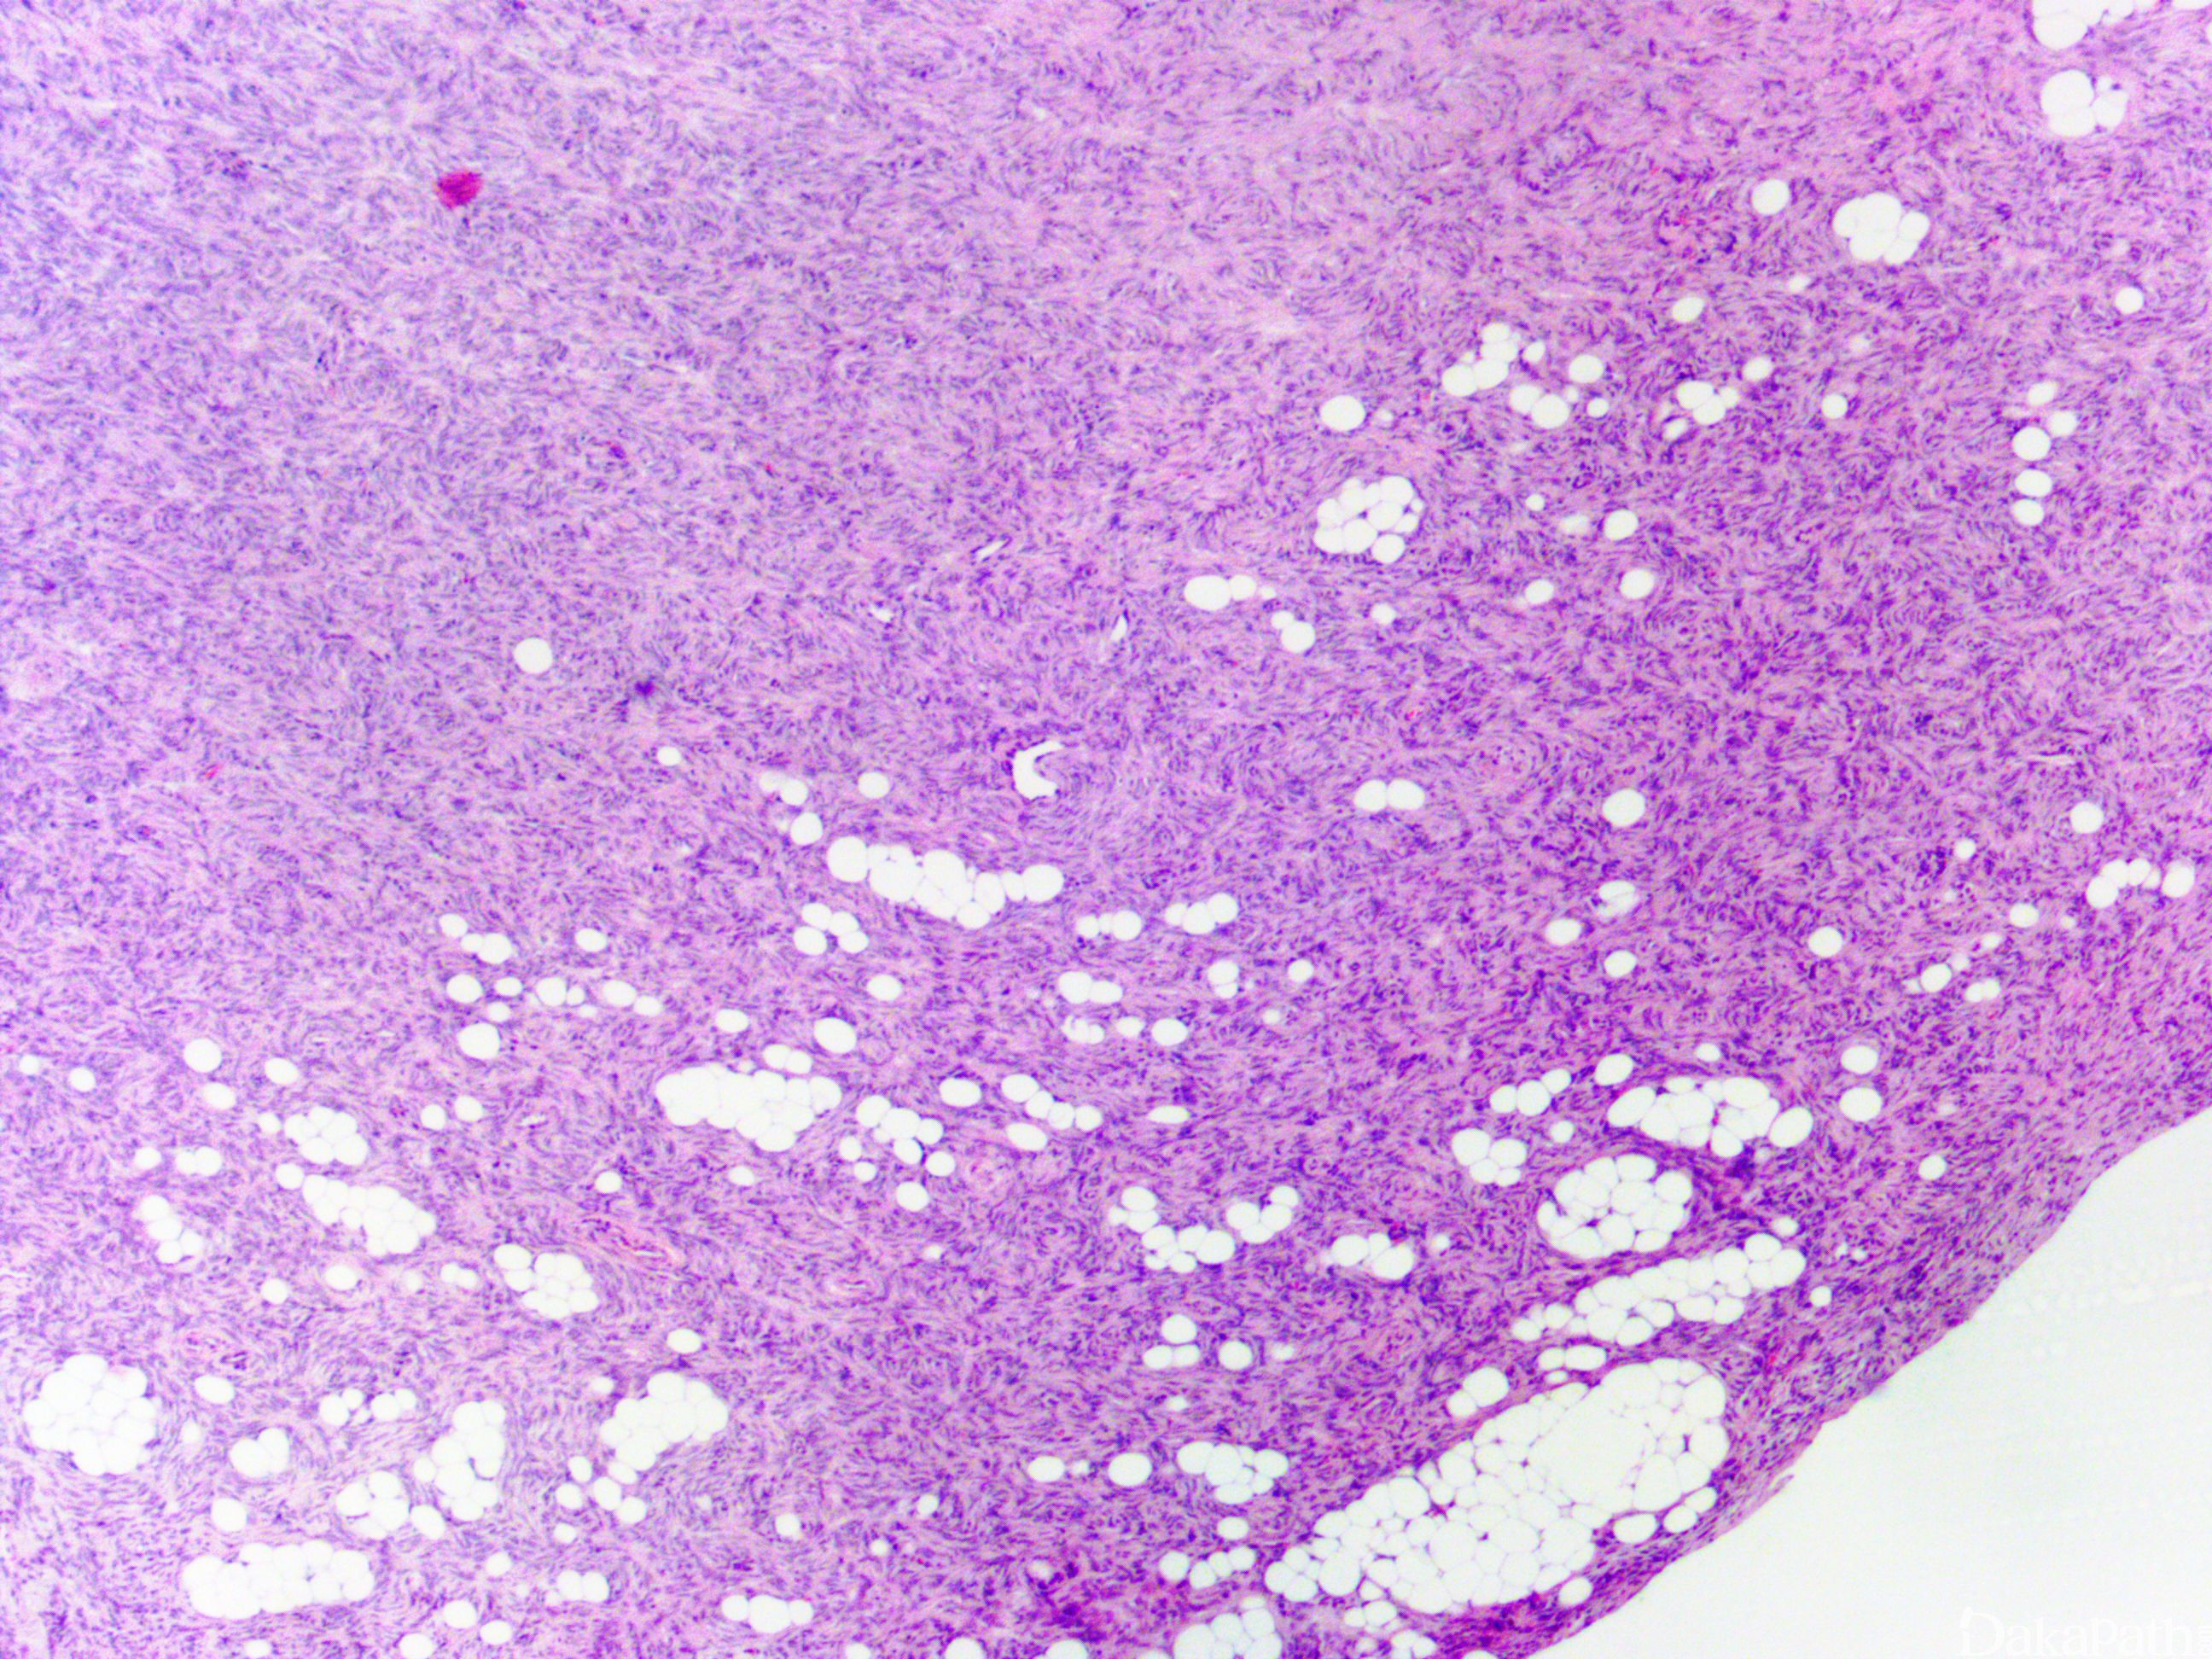

肿瘤主要位于真皮层,弥漫浸润性生长,浸润脂肪组织形成特征性的蜂窝状或蕾丝样 (或称花边样)浸润图像;

部分病例可见局灶的间质黏液变性,黏液区瘤细胞缺乏席纹状结构,瘤细胞呈星芒状,间质微血管网增生明显;

黏液脂肪肉瘤:粘液变异型 DFSP 亦需要与黏液性脂肪肉瘤区别;黏液脂肪肉瘤多位于皮下或肌内,罕见累及真皮,病变内可见复杂的鸡爪样血管网,瘤细胞呈卵圆形,可见单泡或多泡状脂肪母细胞,免疫组化染色表达 S100 蛋白;